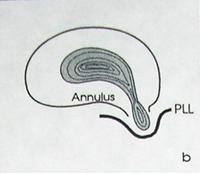

2 стадия — экструзия — выбухание в позвоночный канал элементов фиброзного кольца и дегенерированного пульпозного ядра;

— пролaпс — выпадение в позвоночный канал через дефекты фиброзного кольца фрагментов дегенерированного пульпозного ядра, сохраняющих связь с диском;

Экструзия (трансанулярная) с разрывом продольной связки: